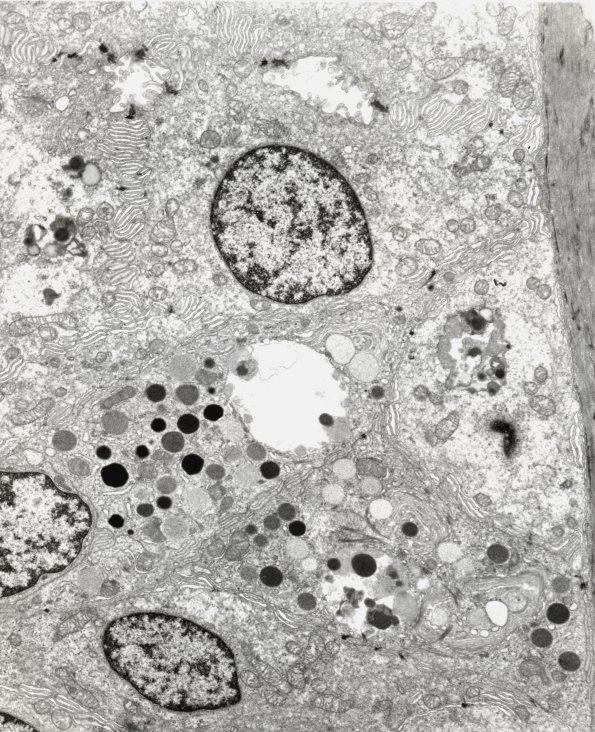

10A1-3 Ultrastructural examination of the skin biopsy shows scattered tiny nerves, small blood vessels and several apocrine and eccrine glands/ducts. In the eccrine ducts scattered large membrane enclosed cytosomes are demonstrated. The cytosomes are lysosome-like bodies containing irregular clumped osmiophilic granular materials admixed with delicate tubular material; however, classical fingerprint and curvilinear bodies are not identified. This material is essentially identical to the skin biopsy of her relative (Case 5 of this section of the atlas) which also resembles material accumulated in the CNS of another family member () whose EMs are not currently available for review. The clinical, family and histopathologic picture in this case is consistent with adult onset ceroid lipofuscinosis. This sweat gland contains a large complex lipopigment aggregate similar to other members of the family presented in a number of cases shown in this section of the atlas. (electron micrographs)